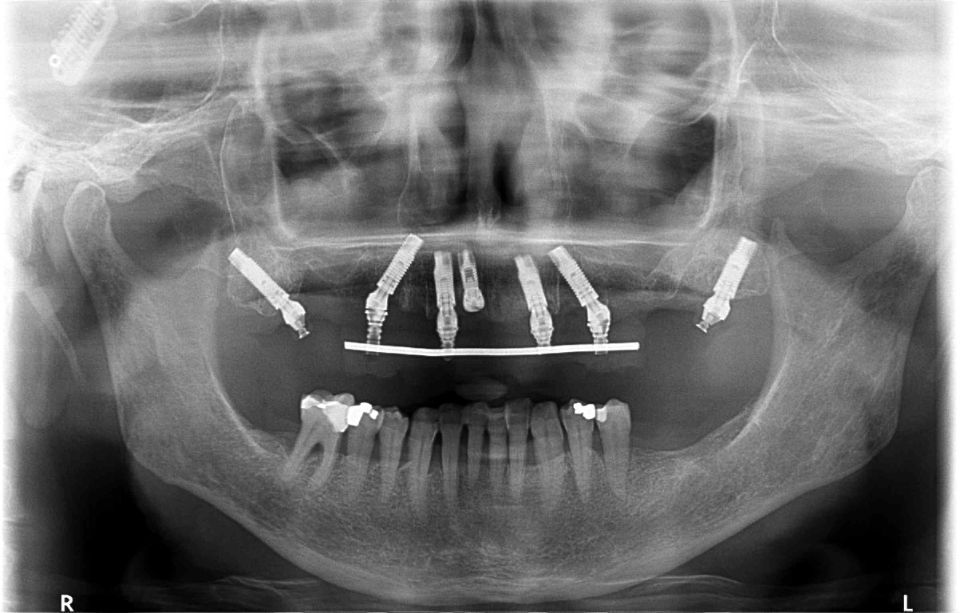

Restorative / Conservative Dentistry

As its name suggests, it tries to preserve by rebuilding teeth that have decayed or fractured, that have suffered trauma or are eroded; to preserve its function as a tooth.

Dental Aesthetics

The appearance of the teeth can be improved. The specialist team will evaluate each case to adopt the most appropriate technique: tooth whitening, composite restorations, ceramic veneers, metal-ceramic crowns, zirconium crowns, orthodontics, periodontal cosmetic surgery ...